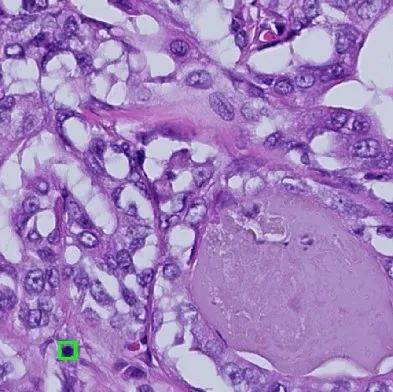

肝组织切片,来源:MEDLIVE

通常,研究人员会采取手术切除、内视镜或针头穿刺吸取等方式,在身体中取出组织切片后交给病理专家。在显微镜观察下,病理学研究人员可以检测肿瘤细胞的发生与发展状况,也可用来确认手术切除是否完全。

框出的“斑点”可能代表组织产生病变,来源:SUTD

除此以外,观测的精度也会有一定的误差。正在进行有丝分裂的细胞通常只有10微米宽,相当于一根头发丝的两百分之一。研究人员在手动注释边界时可能会出现疏漏,导致结果并不准确。